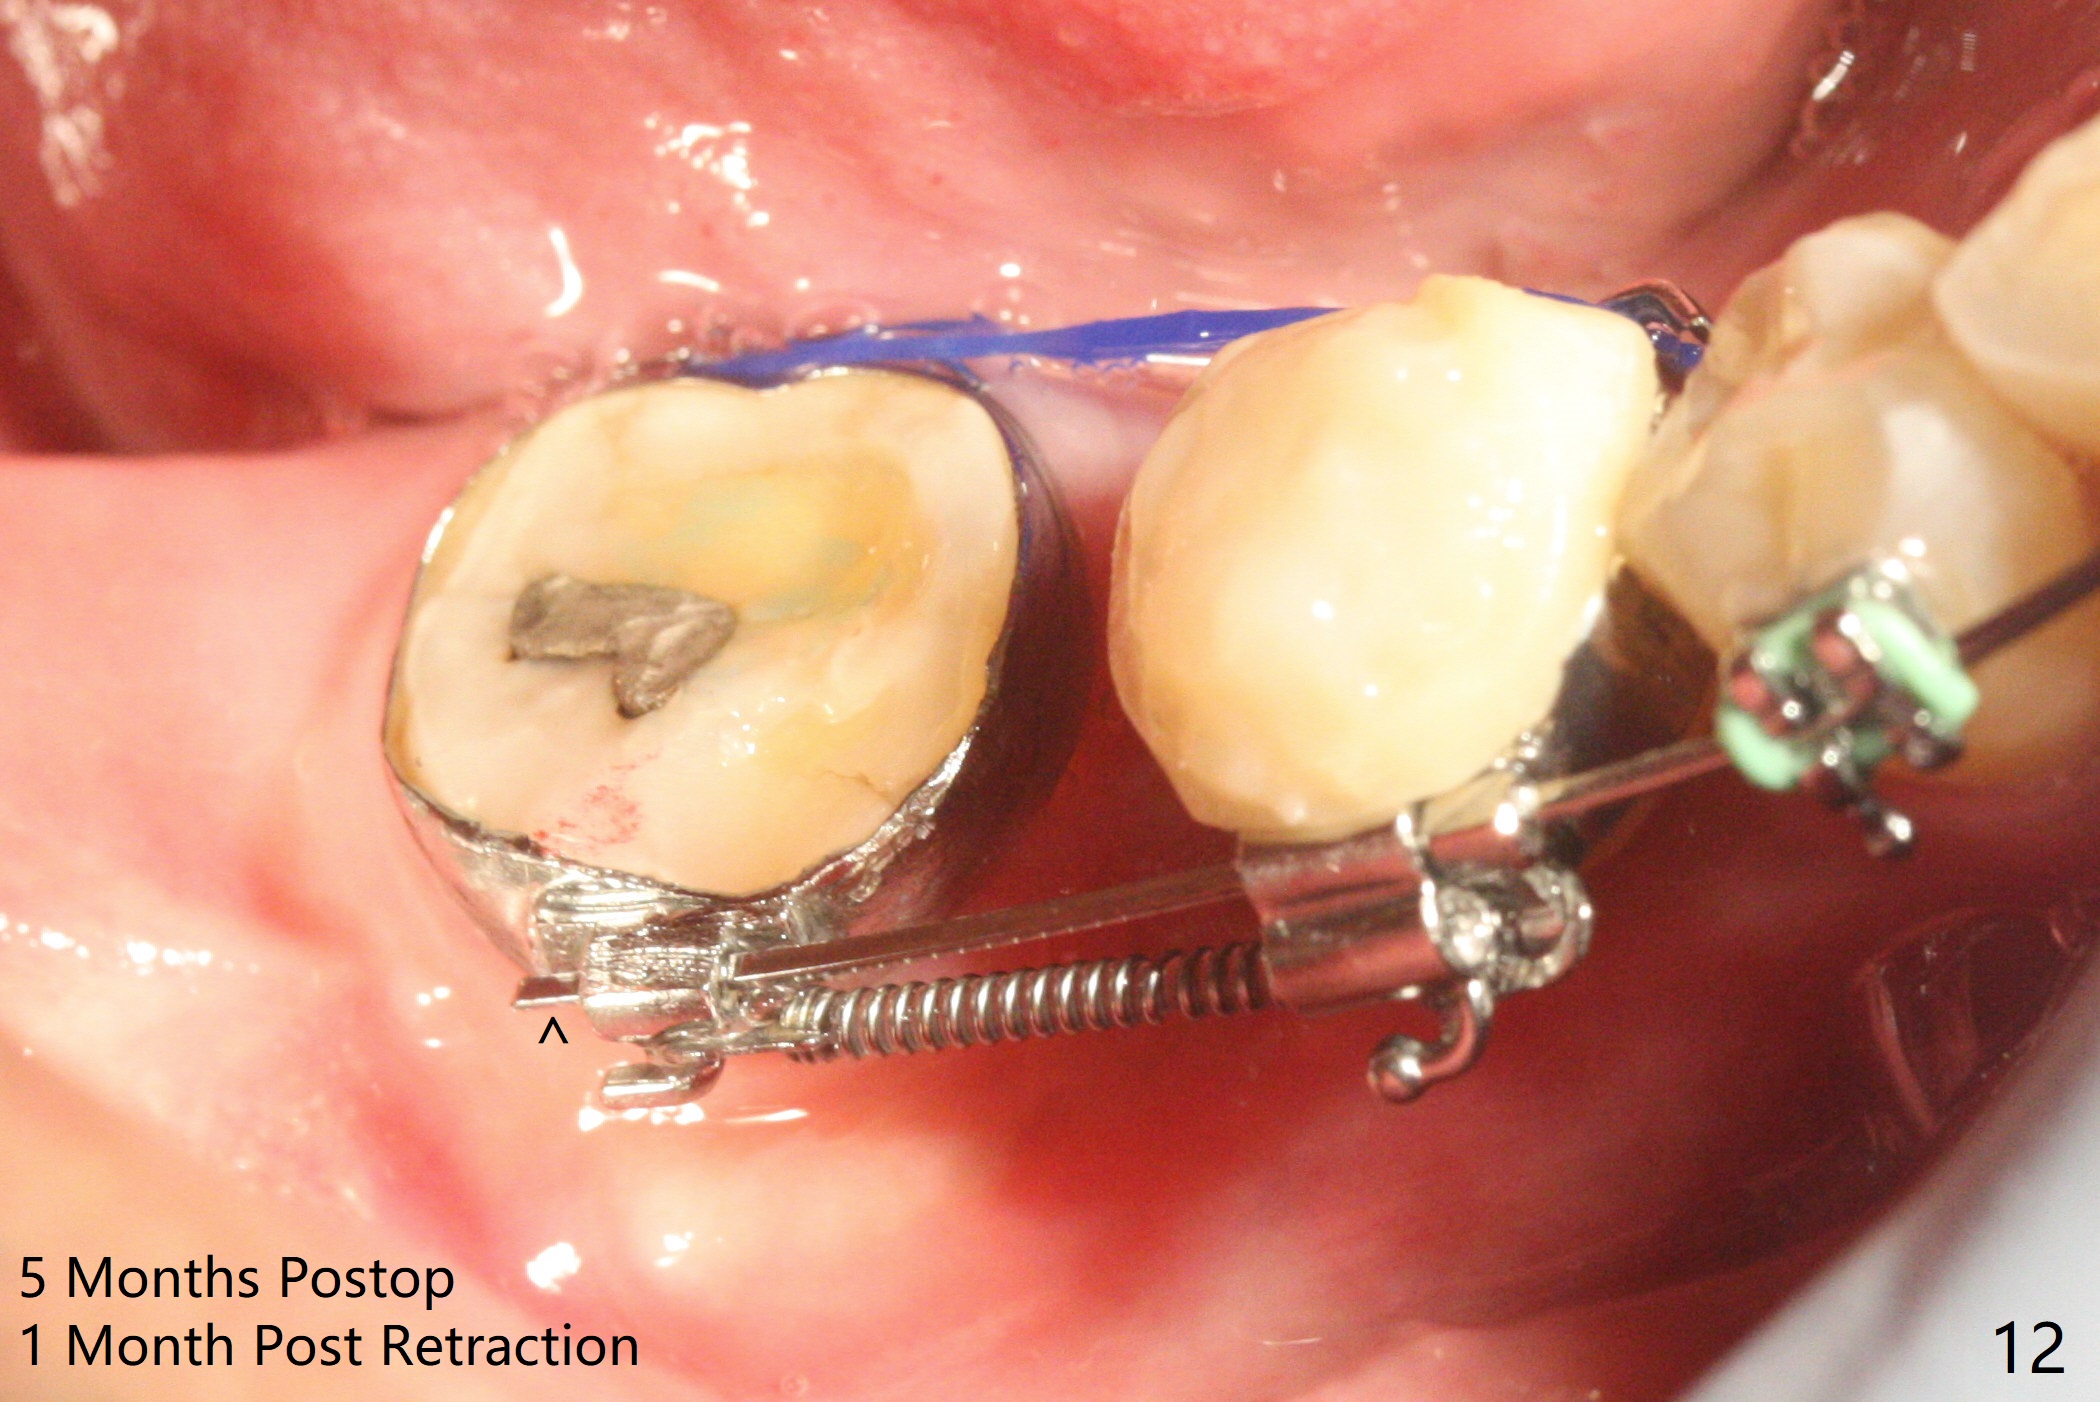

35岁男牙齿矫正后2年5个月右下6远中深龋,拔除后,近中根尖肉芽组织(图零(术前CT冠状切面):*)刮除疼痛,必须阻滞麻醉才能控制疼痛,可能与下牙槽神经分支(图零:红箭头)有关。原先准备在近中牙槽窝近中种植(5x11.5mm),术中发现近中牙槽窝种植好像方便,位置不错,不由自主在那里开始钻洞,由于牙槽窝深,钻洞必须13毫米(图一(接近神经:红虚线)),之后发现钻洞(图二(术前CT3D长轴切面(黑色:近中,远中牙槽窝)):红圆圈)不够理想,使用Lindamann Bur将钻洞往颊侧近中移动(图二:箭头),最终在这方面结果可以(图三,三’,四),虽然接近神经,术后没有神经麻痹。放置粘性骨粉(图四:*),PRF膜,4-0 PGA缝线(图五),最后使用树脂敷料(图六:A)。后牙垂直空间少,术后一周需要降低树脂敷料高度(图七)。术后一个月取出敷料,牙槽窝愈合,植体平台远中稍微暴露(图八),准备一个月后制作临时牙冠。术后两个月植体远中没有暴露,但是基台远中边缘太高了(图九:>),换成6x4毫米愈合基台。下个月换成袖短的修复性基台,安置临时牙冠,牵拉7。舌侧cleats之间放置power chains,颊侧power hooks。其实术后4个月安置临时牙冠和band(图十),牙冠牙合面加高,这样7可以无阻挡移动(图十一:*;16x22 arch wire)。7远中放置power hook行不通,因为末端碰到颊侧前庭牙龈,造成创伤。只好用7颊侧原有牵引勾,在6近中安置一个短的power post (? 图十:箭头),按常规post往下,之间放置12毫米closed spring。如果post往上安置,7牙根牵引可能更有效?近中牵引一个月,第二磨牙前移大约2毫米(图十二:^),稍微近中倾斜,closed spring从12毫米更换到9毫米,舌侧换新的power chains x 4。下一个预约,用sensor 1拍摄根尖片证实第二磨牙近中倾斜,然后在它远中16x22钢丝安放power hook,下缘向颊侧弯曲,避免接触接触粘膜。